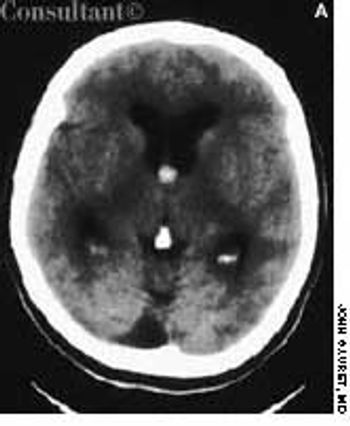

A 60-year-old comatose man was brought to the emergency department (ED). He had a history of diabetes, hypertension, and alcohol abuse. Relatives reported that the patient was noncompliant with his antihypertensive medication regimen.